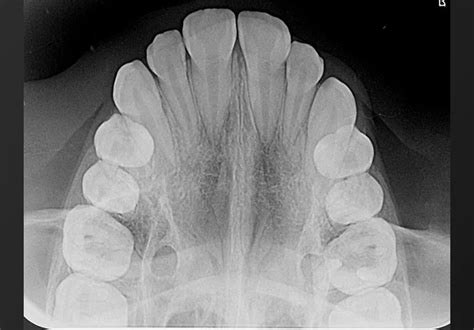

Registros radiográficos pretatamiento y cefalometría

Figura 4 Ortopantomografía pretratamiento.

La ortopantomografía inicial (fig. 4) muestra una dentición mixta, iniciando el segundo período de recambio, con obturaciones a nivel de 16 y 26 y cóndilos mandibulares simétricos.